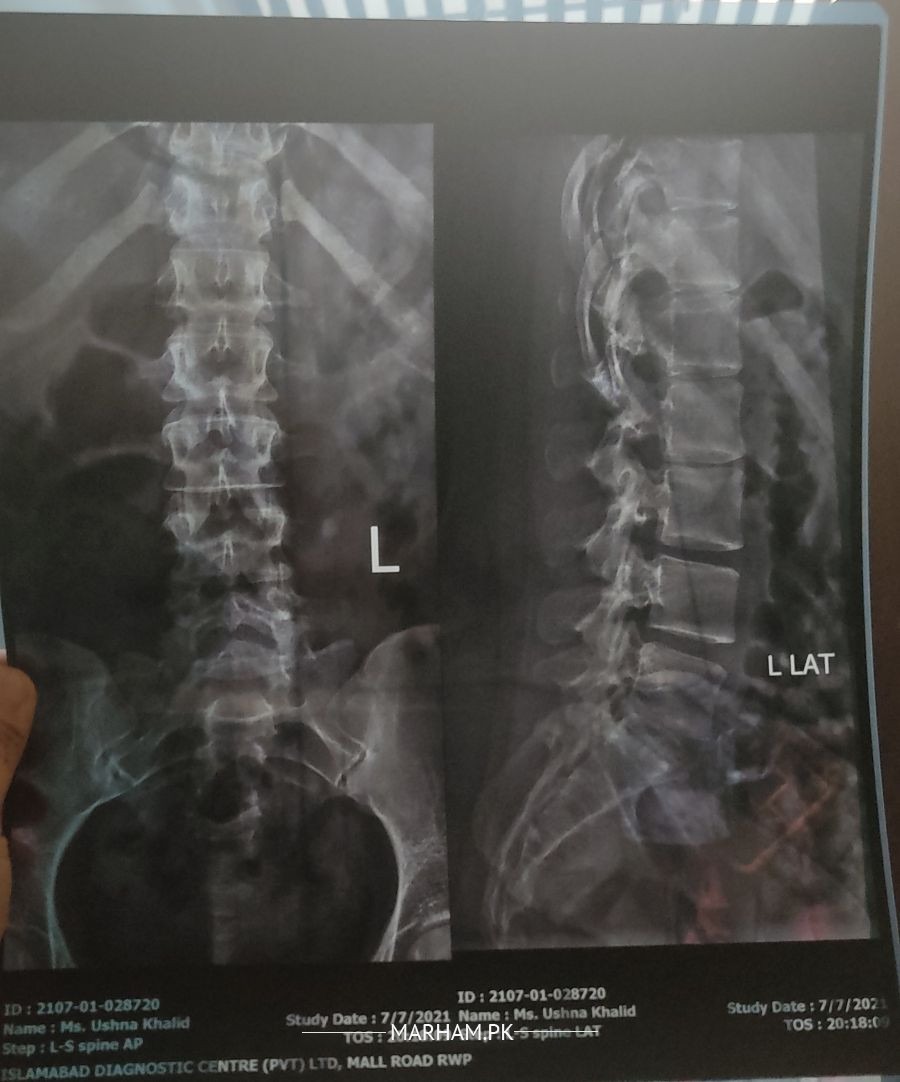

Aoa For the past month, I was dealing with left side back pain and left leg. My pain got worse as I was sitting on my bed without any support. I felt extreme pain in my back and was just like an electric shock so I went for an emergency X-ray I have attached my X-ray in the comments section please tell me what's the problem?

Degenerative changes and lumber straightening could be seen in the film.

This condition is treatable with physiotherapy exercises and guidance. Kindly book an online consultation so that your case could be discussed.

Kamar ka normal curve ma thori changing agyi ha.